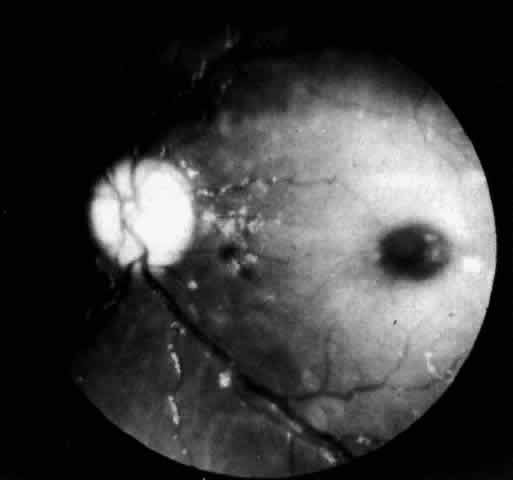

OCULAR MANIFESTATIONS. The retinal changes in Farber's disease are subtle and easily overlooked. The fundi of one 8-month-old patient had been examined several times following the onset of the disease at age 2 weeks and considered to be normal. Cogan and colleagues95 subsequently observed and reported a diffuse grayish opacification of the retina about the fovea, producing a mild cherry-red spot (Fig. 9). The parafoveal opacity differed from that seen in Tay-Sachs disease in that the opacity was pale gray instead of white and it was accompanied by little, if any, pallor of the optic disc. Shortly before death at age 11 months there was a suggestion of a peppery pigmentation of the entire retina and some abnormal pigmentation in the macula. The retinal vessels showed no abnormality. Visual function, as judged by the patient's attentiveness, retention of the optokinetic response, and absence of nystagmus, was normal.

Fig. 9. Fundus of patient with Farber"s disease at age 8 months. Macula shows abnormal grayness with suggestion of cherry-red center. Retinal vessels are normal, and color of disc is normal. (Cogan DG, Kuwabara T, Moser H et al: Retinopathy in a case of Farber"s lipogranulomatosis. Arch Ophthalmol 74:752, 1966. Copyright © 1966, American Medical Association)